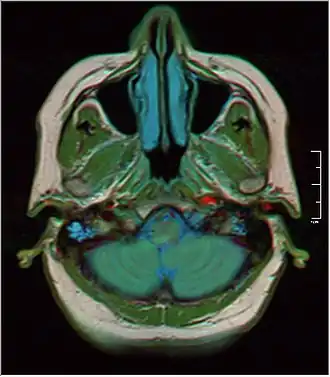

MRI showing fluid in mastoid air cells